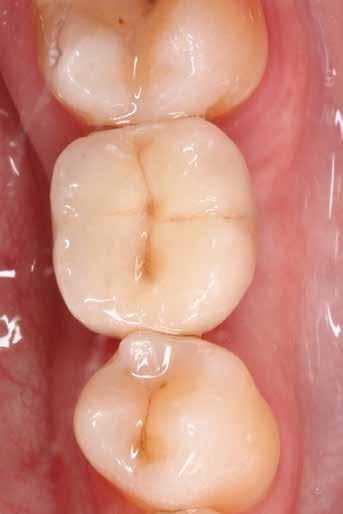

1. ábra: Bal alsó második premoláris foghiány, hagyományos szilikon lenyomat a területről és digitális modell a lenyomat alapján.